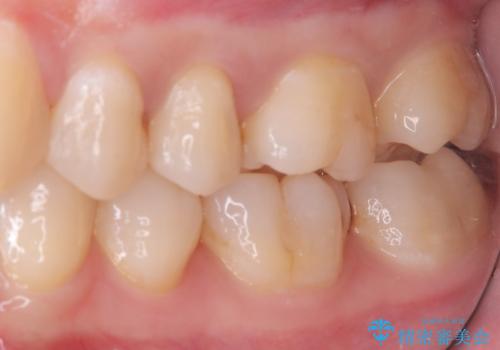

- 主訴:左上真ん中らへんの歯が欠けてしみるので治したい

審美性、適合性の良いセラミックインレーでのやり替えとなりました。

左上4近心に実質欠損を認め、遠心から咬合面にかけてはCR修復が施されていたため、MODインレー窩洞としました。

インレー接着操作時はラバーダム防湿を行っています。